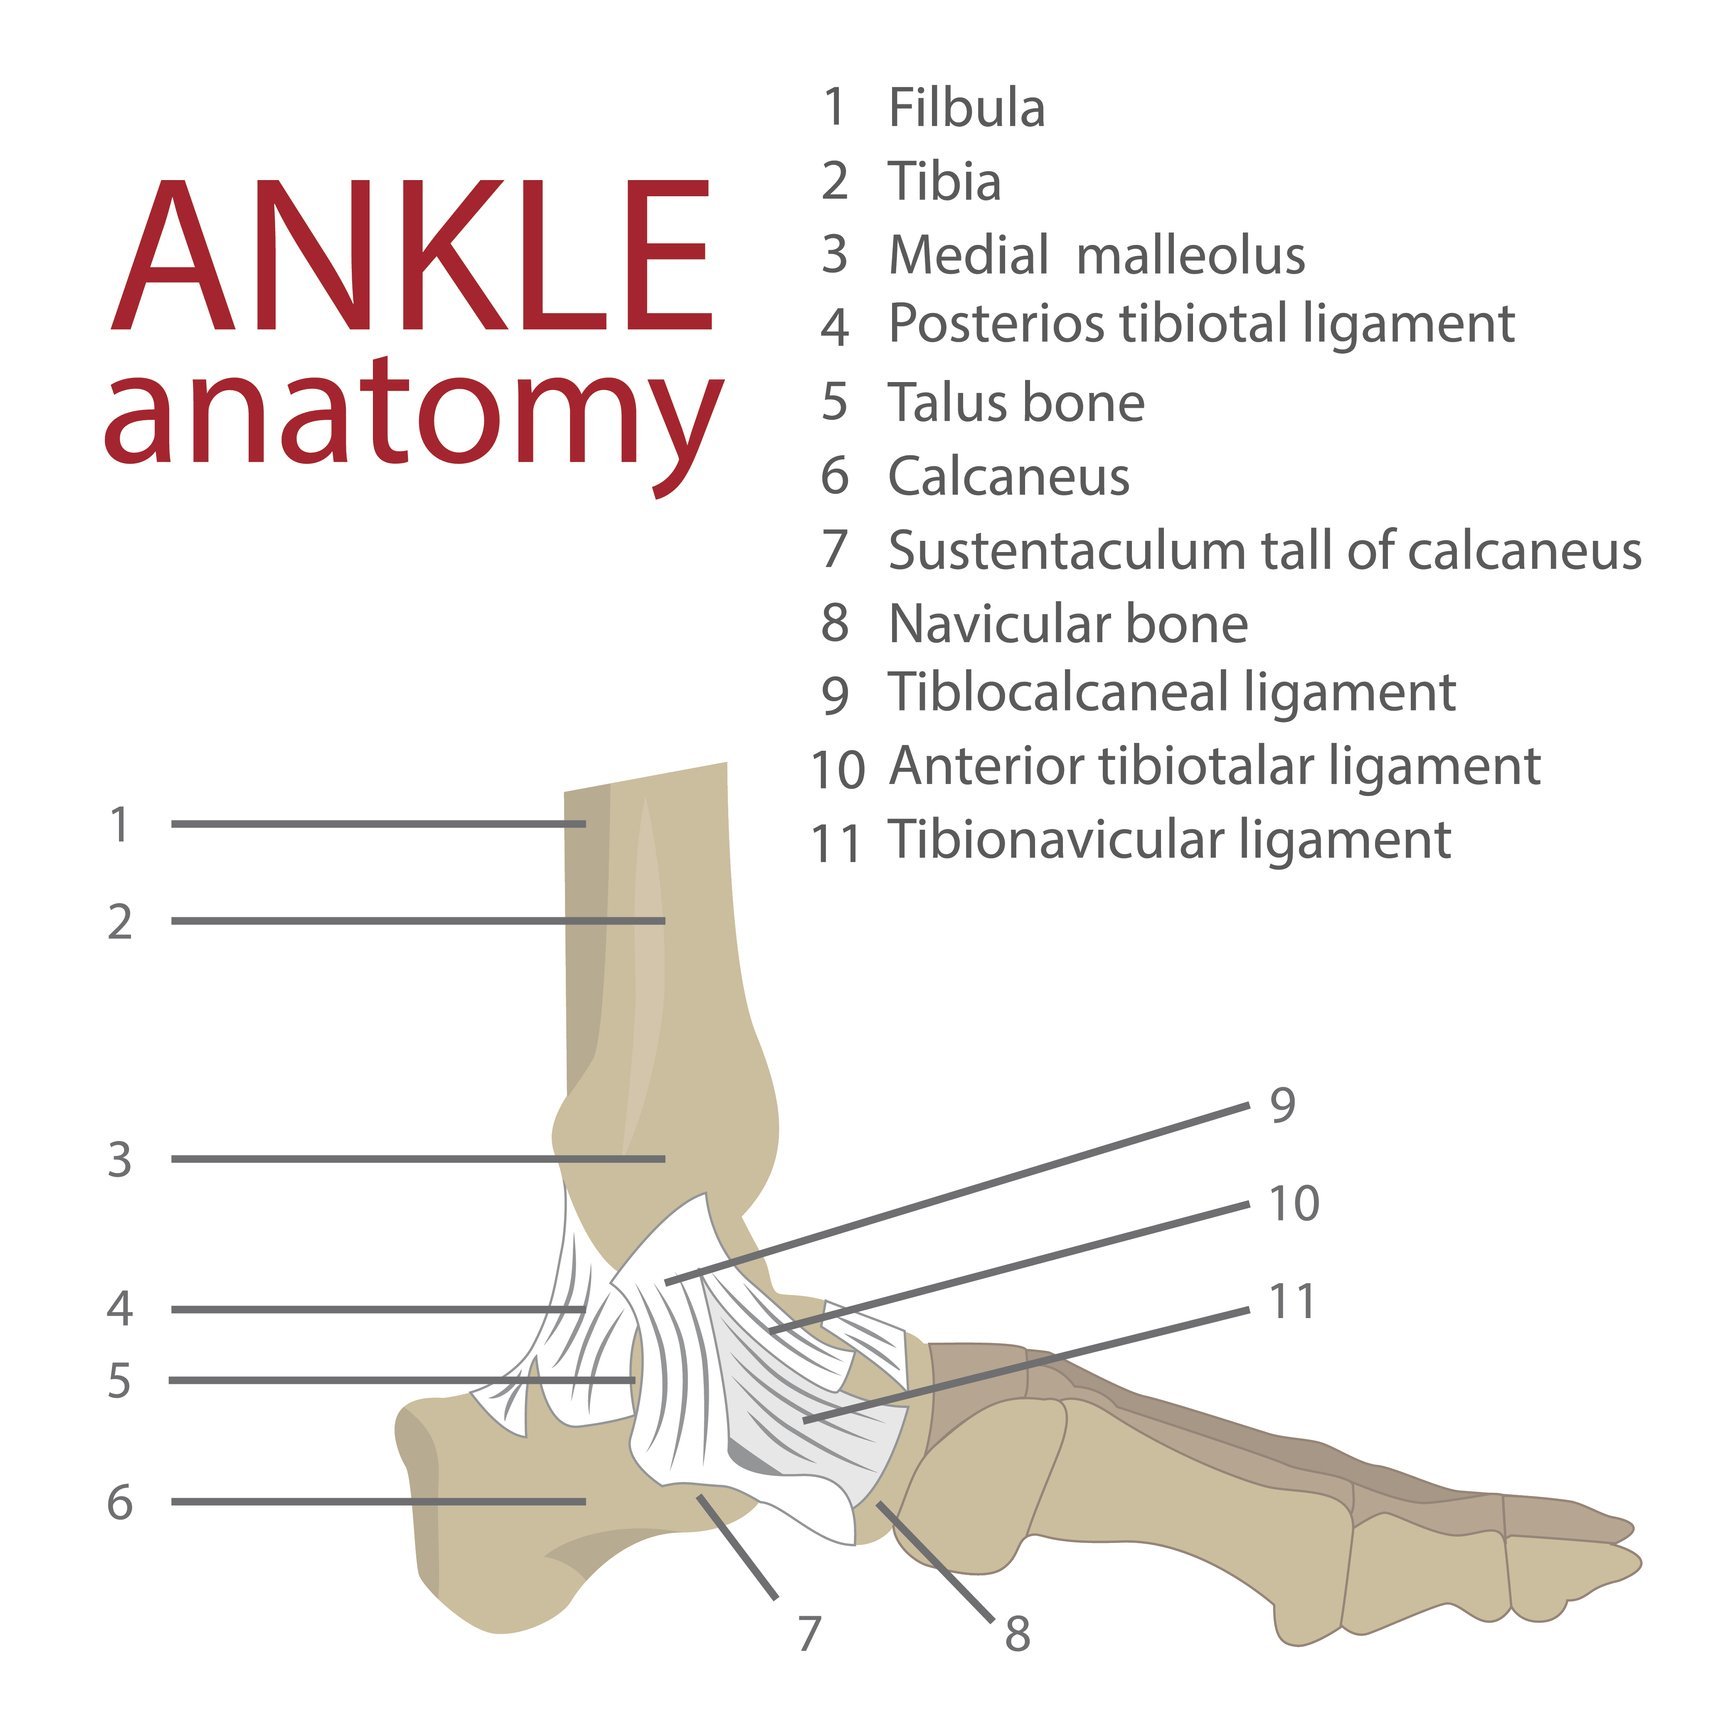

If you have ever “rolled” your ankle, you know what this feels like. A pop in the ankle can happen when fibers of a ligament or tendon tear. This is usually followed by swelling in the area. These are symptoms of a sprain or strain in the ankle.

The most common type of ankle injury is an inversion sprain. This is when the ankle rolls inward and there is tearing in at least one ligament. The first ligament to tear is usually the ATFL or Anterior Talofibular Ligament. The Calcaneofibular Ligament is also common to tear in an inversion sprain.

Bruising and swelling is a sign that there is damage to a ligament, tendon, muscle, or bone in the ankle or foot. When there is damage to tissue, there may be a flood of fluids and blood in the area. This is part of the inflammatory response to the injury.

Difficulyy standing or walking due to foot or ankle pain is one of the most telling signs that you need to see a doctor. If you cannot place weight on the ankle or foot, there may be a fracture or break in one of the bones in the ankle or foot. There are a lot of bones in this area, some are large and some are small. A skilled physician or orthopedic surgeon will likely take an X-ray to see if there is a fracture or some sort of displacement of the bones.

Severe tendon or ligament injuries can also cause limited standing tolerance. These injuries may require an MRI to diagnose them. Continuing to try to stand on these types of injuries can make them worse and make them heal slower. It is important to seek care quickly in these cases.